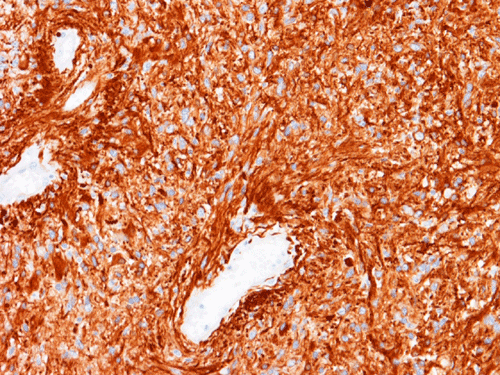

Pathology of the Case: MRI shows a large mass with the more solid component located in the lateral ventricles and the cystic component protruding into the cortical area. The solid area is enhanced (Panel A). On low magnification, the lesion has alternating area of high and low cellularity (Panel B) with scattered calcifications in some of the sections. Medium and high magnification demonstrates perivascular coronary arrangement of cytoplasmic processes (Panel C, D, and E). The nuclei are bland and mitotic figures are not readily seen. Randomly scattered brown pigment containing cells are found in multiple areas of the tumor (Panel F, G, and H). Scant lipidized cells with enlarged nuclei (Panel I) are also present. The tumor cells are strongly positive for glial fibrillary acidic protein (GFAP) (Panel J and K) and S100 protein but are negative for epithelial membrane antigen (EMA), neurofilament proteins, and NeuN. The overall Ki67 labeling is low but focal small areas (about the size of one high power field) has increased labeling. The pigment appears to be melanin on microscopic examination. These pigments are positive with Fontana-Masson stain (Panel L) but negative for Prussian blue stain for iron (Panel M). These features confirmed that these are melanin pigments. The pigment granules are positive for periodic acid-Schiff reaction (N), negative for Ziehl-Neelsen (acid fast) stain..

Immunohistochemistry

Ependymomas often display significant amount of immunopositivity for glial fibrillary acidic protein (GFAP). They are often but not always positive for epithelial antigen (EMA). The lumninal surface of ependymal rosettes can be strongly positive for epithelial membrane antigen. The same is true for the surface of papillary ependymal ependymoma. EMA positive reaction can also occur as positive dots in tumor cells. The staining can have a cluster pattern of distribution. However, most tumors are only focally positive.